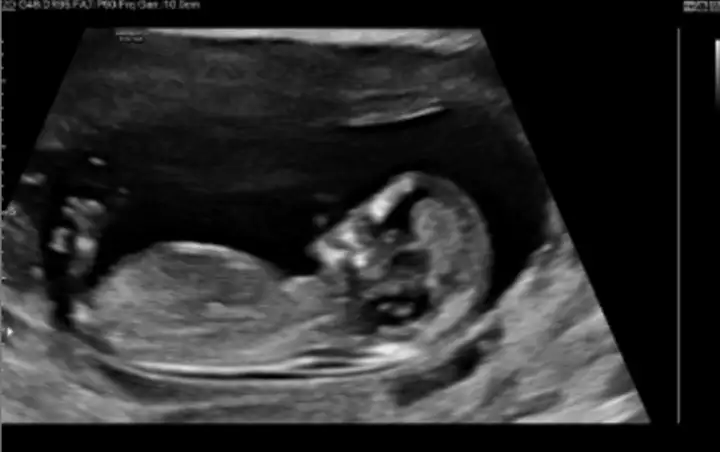

Selam kizlar 13-14 hafta sizce ne?